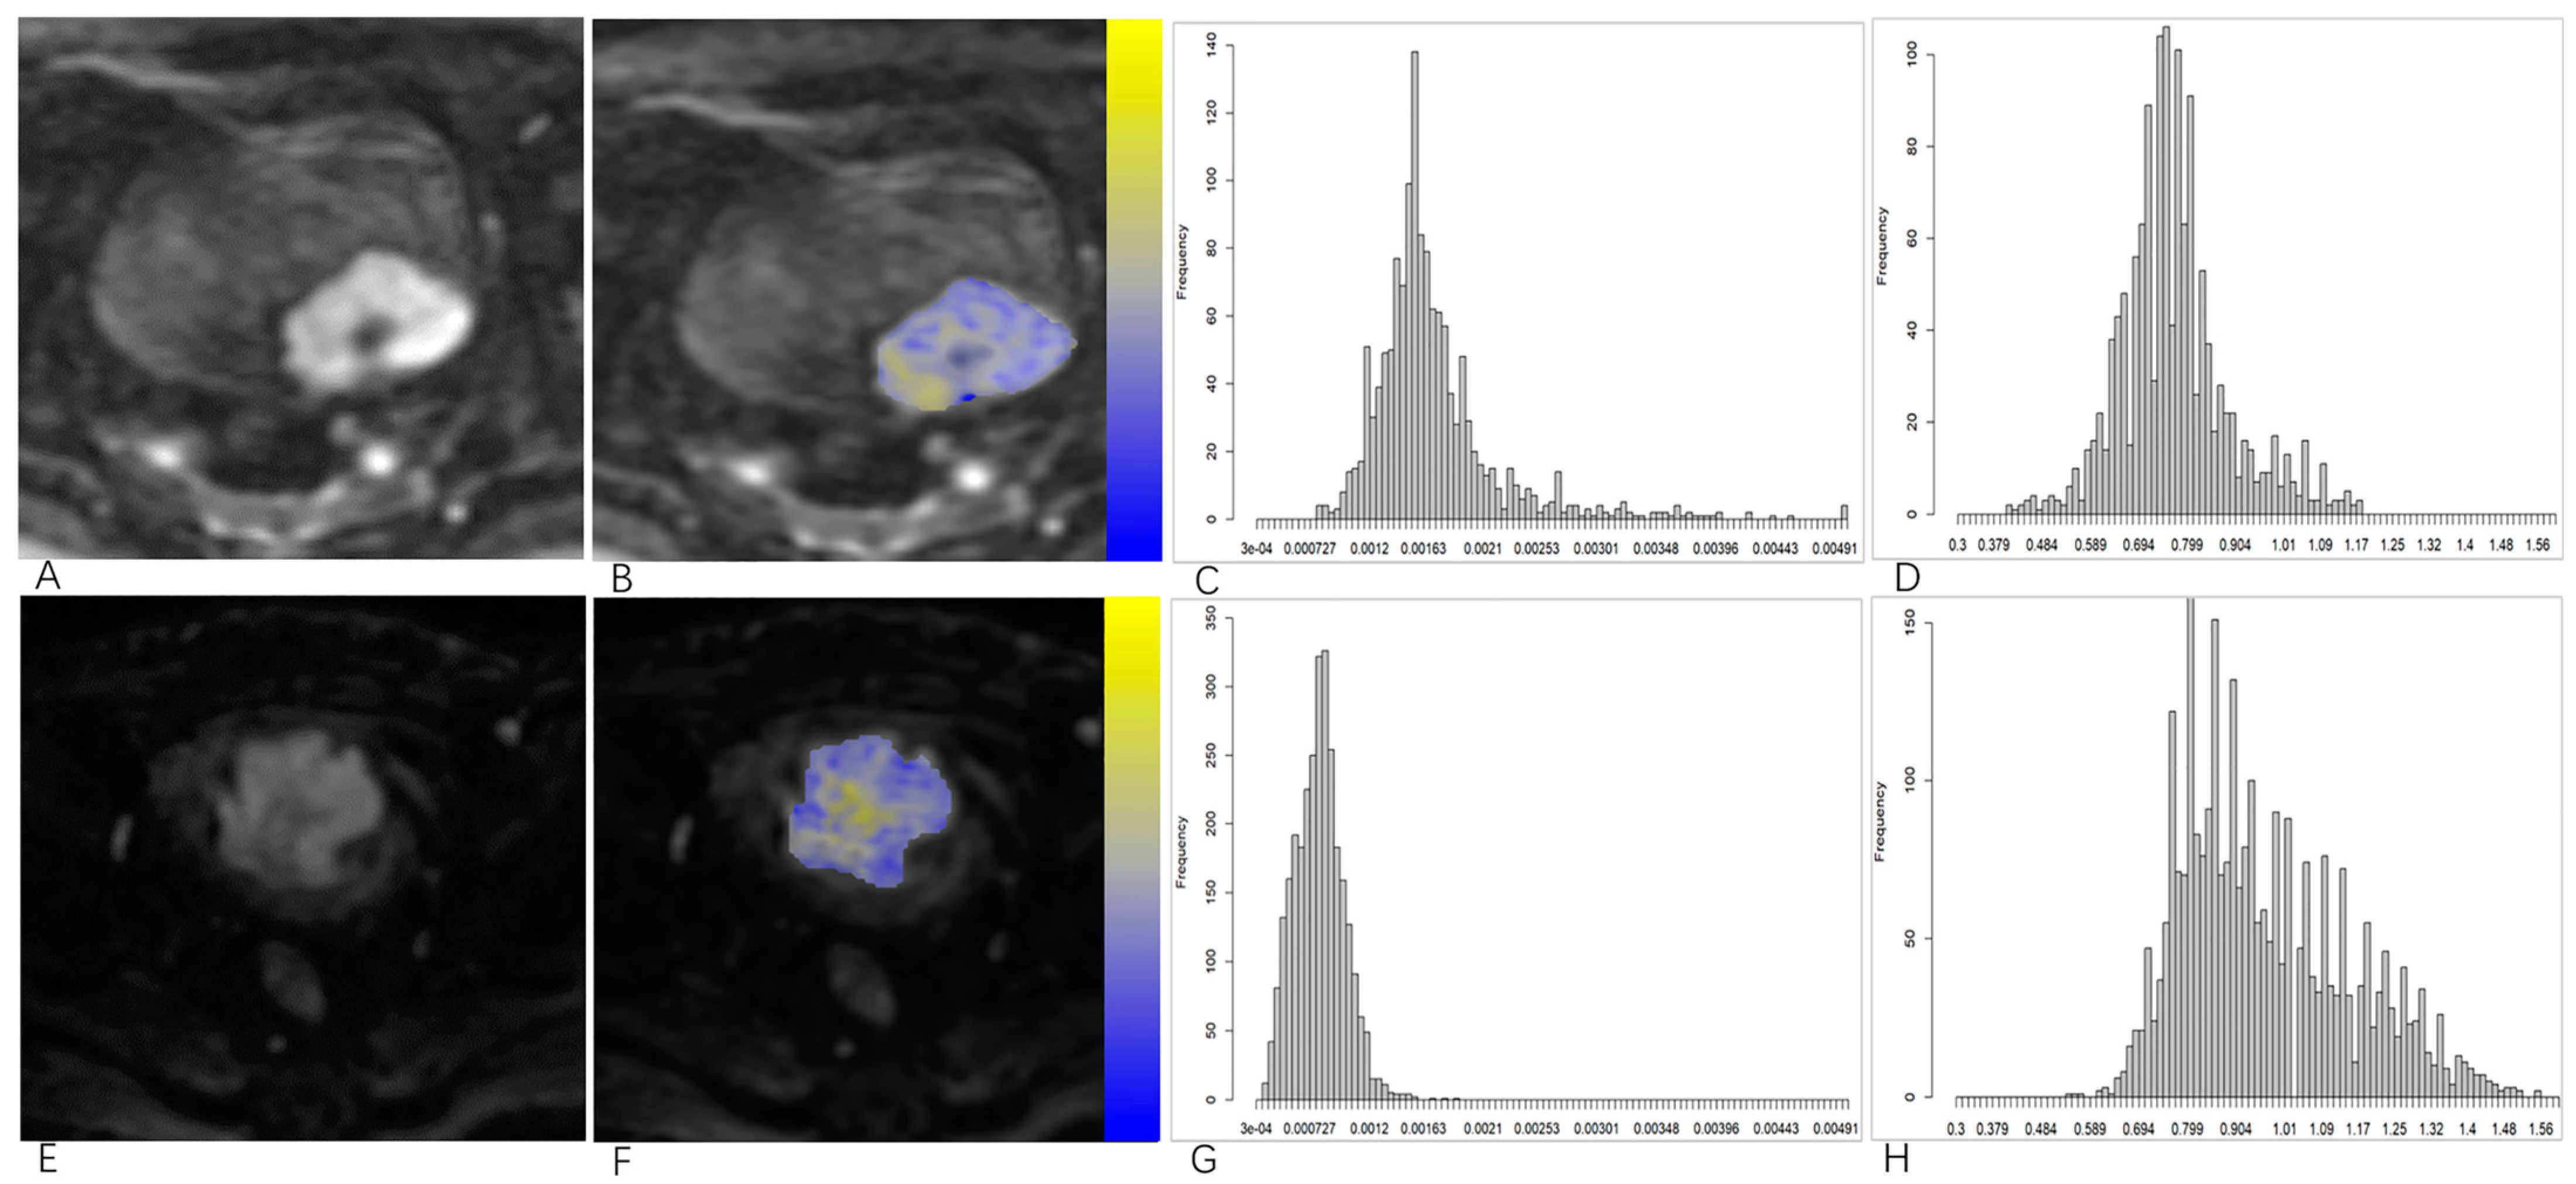

2.3. Image Processing and Analysis